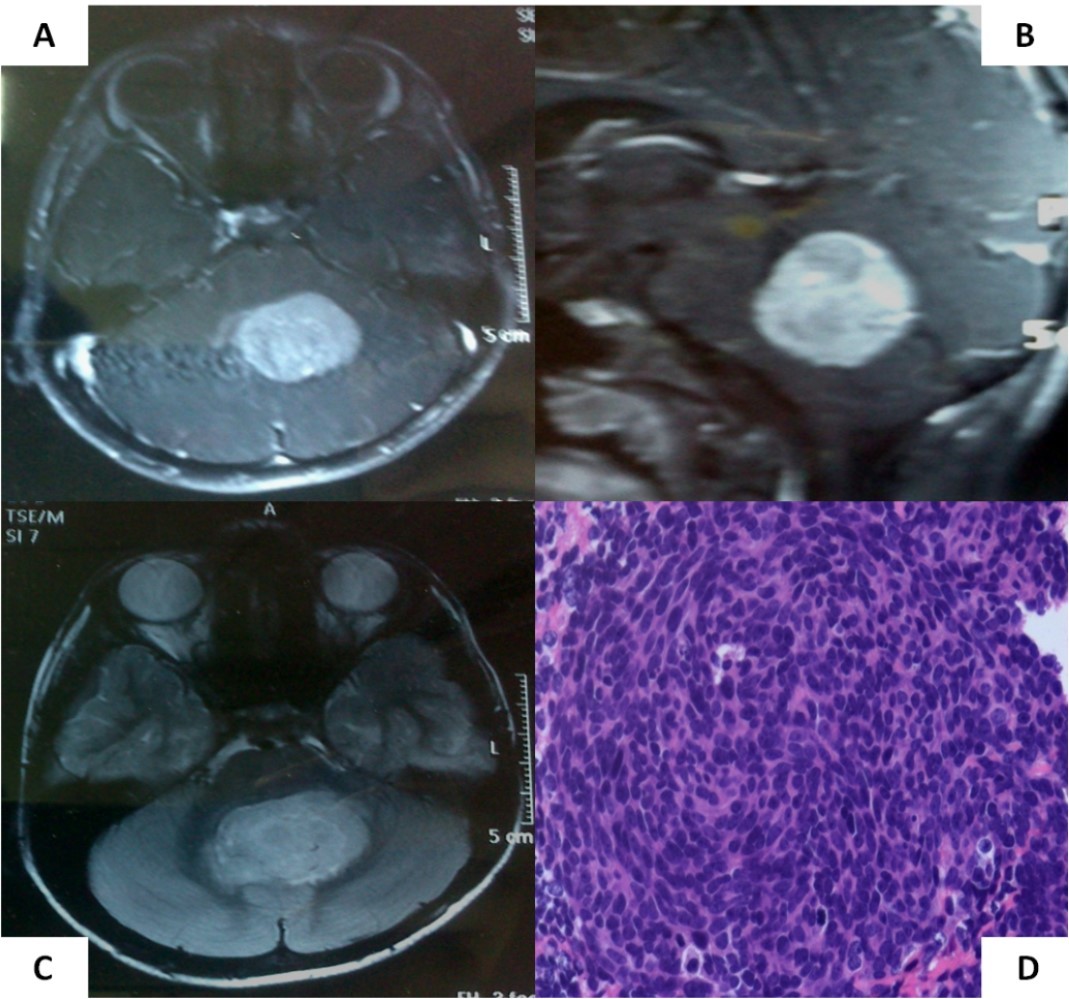

A 6-year old boy initially presented to us with headache, vomiting, and ataxia of 6-months duration. Cranial magnetic resonance imaging (MRI) showed a large lobulated, midline vermian space-occupying lesion, hypo-to iso-intense on T1-weighted images, hyperintense on T2-weighted and FLAIR images with prominent and homogenous enhancement post-contrast (Figure 1A-C) with aqueductal compression causing supratentorial hydrocephalus suggestive of medulloblastoma. He underwent near-total excision of the vermian space occupying lesion at an outside hospital that was reported as classical medulloblastoma on conventional light microscopy (Figure 1D). The non-availability of formalin-fixed paraffin embedded tumor tissue blocks precluded further molecular subgrouping of medulloblastoma. Post-operative MRI revealed the presence of two small residual enhancing nodules at the edge of the resection cavity. Neuraxial staging using MRI of the spine with gadolinium and cerebrospinal fluid (CSF) malignant cell cytology via a lumbar puncture did not show any evidence of leptomeningeal dissemination. Although there was no evidence of leptomeningeal metastases (M0 status), he was categorized as high-risk disease by virtue of residual tumor volume >1.5 X 1.5cm2 as per the prevalent risk-stratification system, and treated on an ongoing institutional phase II study of concurrent carboplatin with standard-dose craniospinal irradiation with posterior fossa boost followed by six cycle of multi-agent adjuvant systemic chemotherapy. Neuraxial imaging after completion of adjuvant therapy showed complete resolution of residual enhancing nodules with reactive gliosis.

Figure 1.Pre-operative MRI of the brain showing a brilliantly enhancing midline vermian lesion in axial (A) and sagittal (B) T1-weighted post-contrast images with variable intensity on T2-weighted images (C). Photomicrograph of the tumor (D) showing it highly cellular tumor composed of small blue round cells consistent with classic medulloblastoma (X 400, hematoxylin & eosin)